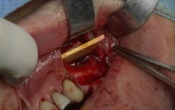

Comblement sinusien avec utilisation d'une lame de phosphate tricalcique